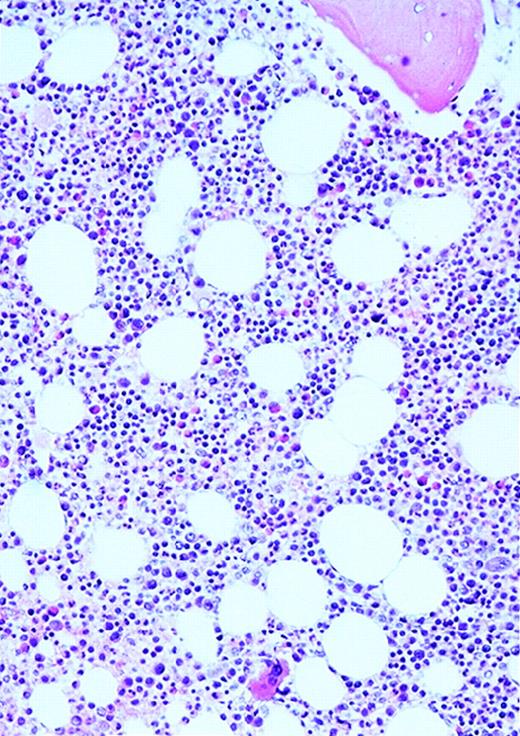

The patients with AML consisted of 8 women and 12 men; the control patients consisted of 12 women and 8 men. The mean age of the AML patients was 59 years (range, 24-87 years). In the control group, the mean age was 49 years (range, 27-71 years). The FAB distribution of the AML cases was as follows: 2 M0, 6 M1, 6 M2, 4 M4, and 2 M7. The cellularity (average ± SEM) was 78% ± 26% (range, 25% to 100%) and 49% ± 8% (range, 35% to 65%) for AML and normal marrows, respectively (P < .0001). Using ULEX-E staining, AML marrows had (average ± SEM) 8.3 ± 3.6 vessels/mm (range, 3.7-19.3) while normal marrows had 4.3 ± 1.8 vessels/mm (range, 1.6-7.9). Using vWF staining of the same specimens, AML marrows had 8.6 ± 3.0 vessels/mm (range, 3.7-15.8) and normal marrows had 4.9 ± 2.2 vessels/mm (range, 1.5-10.1). The differences between the numbers of vessels/mm in AML and normal marrows were highly significant (P < .0001 for both ULEX-E and vWF staining). ULEX-E and vWF exhibited similar staining patterns. Figures1 and 2 show examples of vascularity in normal and AML marrows.

Vascularity of normal and AML marrow specimens.

Normal or AML bone marrow samples were stained with H&E or for vWF expression (see Methods) for vessel scoring. Legends (all ×200): A = normal bone marrow with H&E stain; B = normal bone marrow with vWF stain; C = AML bone marrow with H&E stain; D = AML bone marrow with vWF stain. The normal bone marrow shows strong staining for vWF in megakaryocytes but no evidence of increased vessels. The AML marrow has significantly more vessels than the normal marrow. These sections are representative of the whole series.